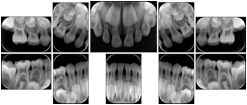

Intra-oral radiography typically involves acquisition of multiple images of various parts of the dentition. Many digital radiographic systems offer customized templates that are used for displaying the images in a study on the screen. These templates may also be referred to as mounts or view sets. The Structured Display Object represents a standard method of encoding and exchanging the layout and intended display of Structured Displays. A structured display object created in this manner could be stored with a study and exchanged with images to allow for complete reproduction of the original exam.

1. A patient visits a General Dentist where a Full Mouth Series Exam with 18 images is acquired. The dentist observes severe bone loss and refers the patient to a Periodontist. The 18 images from the Full Mouth Series along with a Structured Display are copied to a DICOM Interchange CD and sent with the patient to see the specialist. The Periodontist uses the CD to open the exam in his Dental Radiographic Software and consults via phone with the General Dentist. Both are able to observe the same exam showing the images on each user's display using the exact same layout.

Intra-oral Full Mouth Series Structured Display

Figure OO-1. Intra-oral Full Mouth Series Structured Display